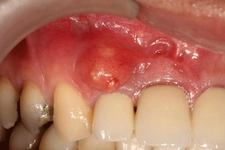

Diş ekimi, günümüzde oldukça yaygın bir işlem olmasına rağmen, her cerrahi müdahalede olduğu gibi bazı riskleri de beraberinde getirebilir. Enfeksiyon ve vücut reddi, bu işlemin potansiyel komplikasyonları arasında yer alır. Ancak, bu riskler uygun önlemlerle önemli ölçüde azaltılabilir.